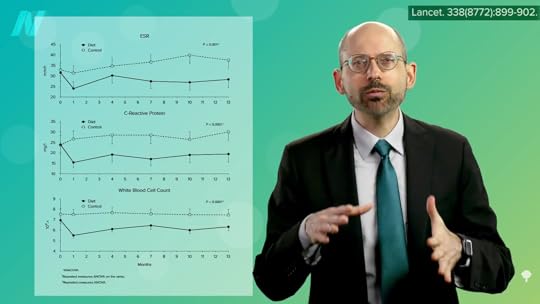

The evidence base started with case reports of water-only fasting followed by a plant-based diet. There were remarkable reports of years of pain and stiffness that were not only gone within a week but, more importantly, stayed gone on the healthier diet. One after another, just like that. But case reports are merely glorified anecdotes. There have been studies going back decades suggesting that “fasting may represent the most rapid and most available way of inducing relief of arthritic pain and swelling for patients who have RA,” rheumatoid arthritis, but they often failed to control for the placebo effect, which is “particularly important whenever self-reporting systems are used (reports on general well-being, pain, stiffness, tiredness, and the like)”—that is, subjective symptoms. There are objective measures, however, including lab tests of inflammation that don’t appear to be affected by placebos. As shown below and at 3:22 in my video Fasting for Rheumatoid Arthritis is what can be seen in controlled trials, starting immediately and staying down for at least a year.

Ten different measures of inflammation decreased significantly after the fasting and subsequent meat- and egg-free diet, whereas none of the parameters budged in those individuals with rheumatoid arthritis who continued to eat their regular diets. What’s more, this squelching of inflammation translated into a significant reduction in pain, morning stiffness, loss of grip strength, and the number of tender and swollen joints, as you can see below and at 3:43 in my video.

Even a year after the trial had ended, those who benefited from the diet continued to benefit in terms of less pain, stiffness, and tender and swollen joints, presumably because they stuck with it, as shown here and at 4:00 in my video.